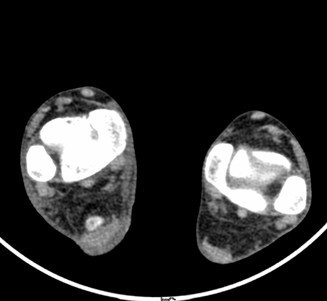

患者男,15岁,因“车祸致右足跟部皮肤撕脱伤清创缝合术后13天”入院。患者13天前因车祸导致右足疼痛流血伴功能障碍,右足跟部皮肤撕脱,遂到当地人民医院就诊,诊断为右跟骨骨折伴跟部皮肤严重剥脱伤,右胫骨远端骨折。急诊下行“右足跟部皮肤严重剥脱伤皮肤严重挫裂伤清创缝合术”。术后给予止痛、消肿、预防感染等对症处理,目前右足外侧及跟部皮肤变暗,坏死。患者为进一步诊疗,故转入我科继续治疗。

查体:右足内踝、外踝及跟部皮肤变暗,部分缺血坏死。未见畸形,稍肿胀。右足趾皮温无明显降低,右足趾感觉未见明显异常。右足内踝、外踝及跟部皮肤局部压痛。右踝关节活动受限,右踝关节活动诱发疼痛。右膝关节活动未见明显异常。 辅查:x片示右跟骨,右胫骨远端骨折。

诊断:1、右足清创缝合术后皮肤软组织坏死伴感染,2、右跟骨骨折,3、右胫骨远端骨折。 治疗:择期手术。

足部撕脱伤因其血供差而不易愈合,损伤后最好争取一期缝合血管、神经等组织,有利于创伤愈合;愈合不佳的则要二期植皮。